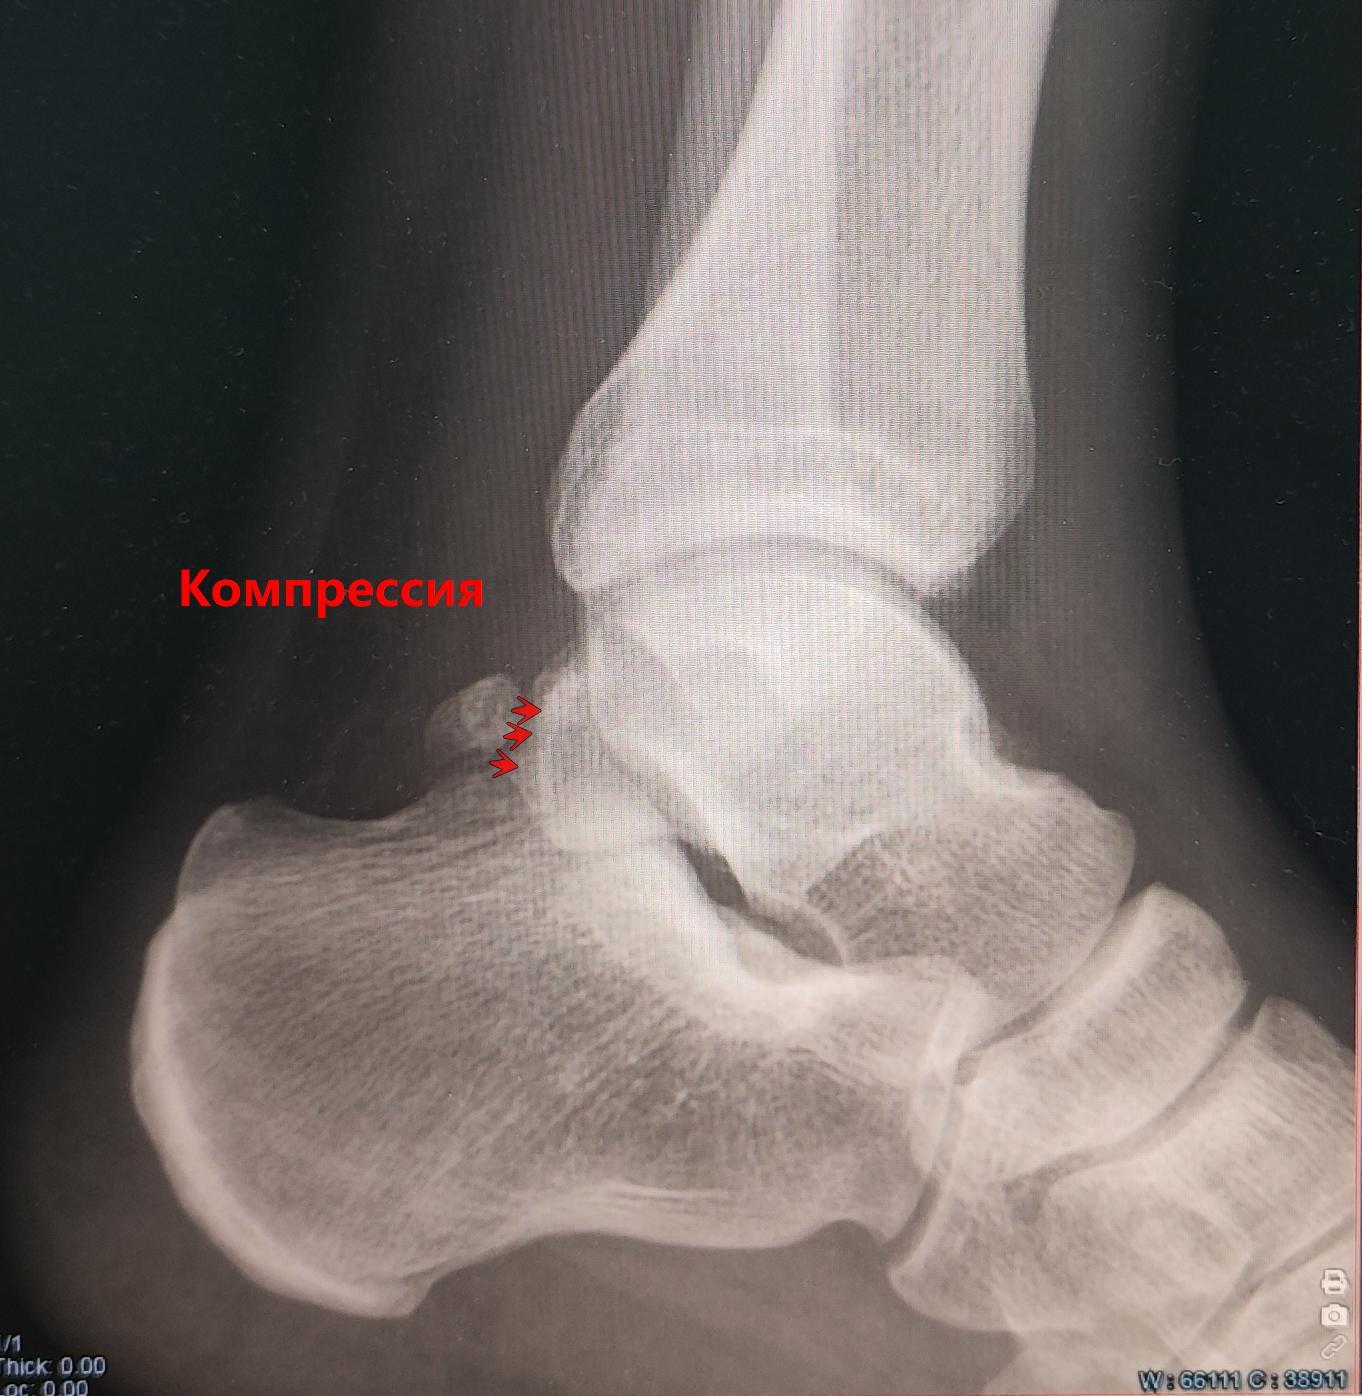

Описание: на Р-граммах левого гс/с в 2х проекциях суставная щель не сужена, субхондральный склероз, краевые остеофиты-не выявлены. По заднему контуру таранной кости определяется наличие дополнительной кости-os trigonum. Заключение:Os trigonum(аномалия развития левой стопы), наиболее вероятно вызывающая синдром компрессии таранной кости.

Может вызывать задний импиджмент голеностопа — боль при тыльном сгибании стопы.